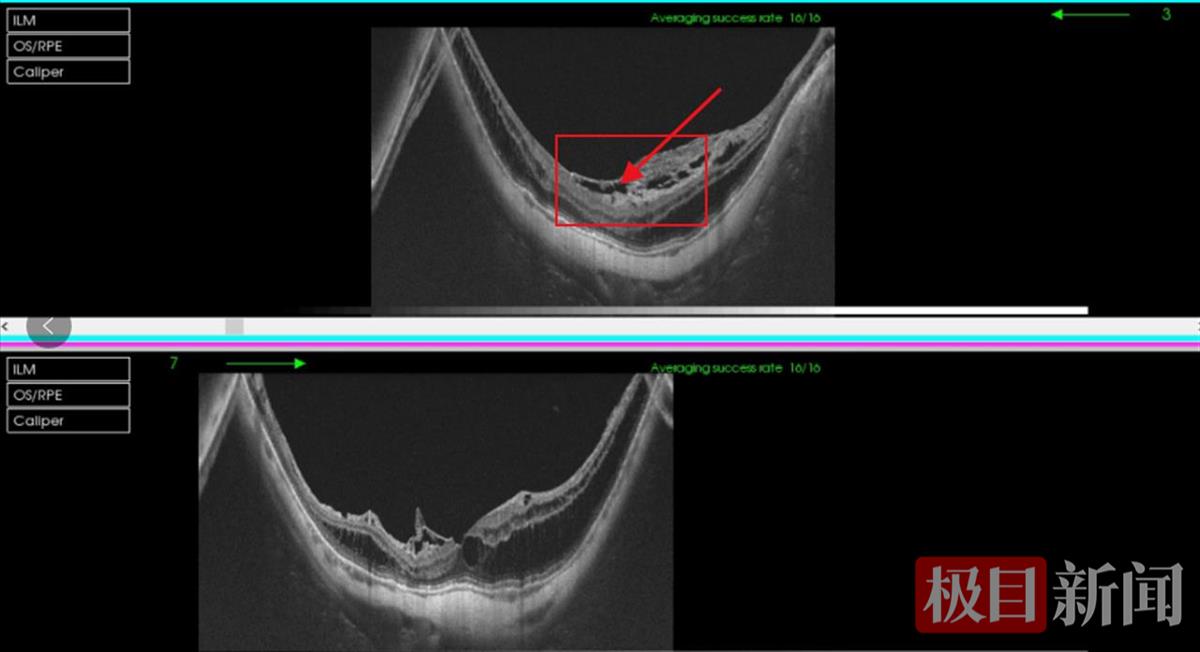

爱尔眼科医院湖北省区总院长邢怡桥教授了解到,方婆婆高度近视,双眼近视度数有1000度左右,检查发现做过白内障摘除手术的她植入眼内的人工晶体及张力环囊袋复合体已脱位至玻璃体腔,进一步散瞳检查发现她的眼底视盘旁萎缩弧明显,黄斑区可见弥散性脉络膜萎缩。完善进一步辅助检查后,方婆婆被诊断为右眼视网膜劈裂症、右眼黄斑前膜、右眼人工晶体脱位、双眼高度近视,右眼需要进行手术治疗。

方婆婆的视网膜组织发生分离 (湖北爱尔眼科医院供图)

11月4日,方婆婆来到湖北爱尔眼科医院住院治疗。11月7日,邢怡桥教授为她进行了手术。出院两周复查时,方婆婆视力提高、视物变形情况得到改善。